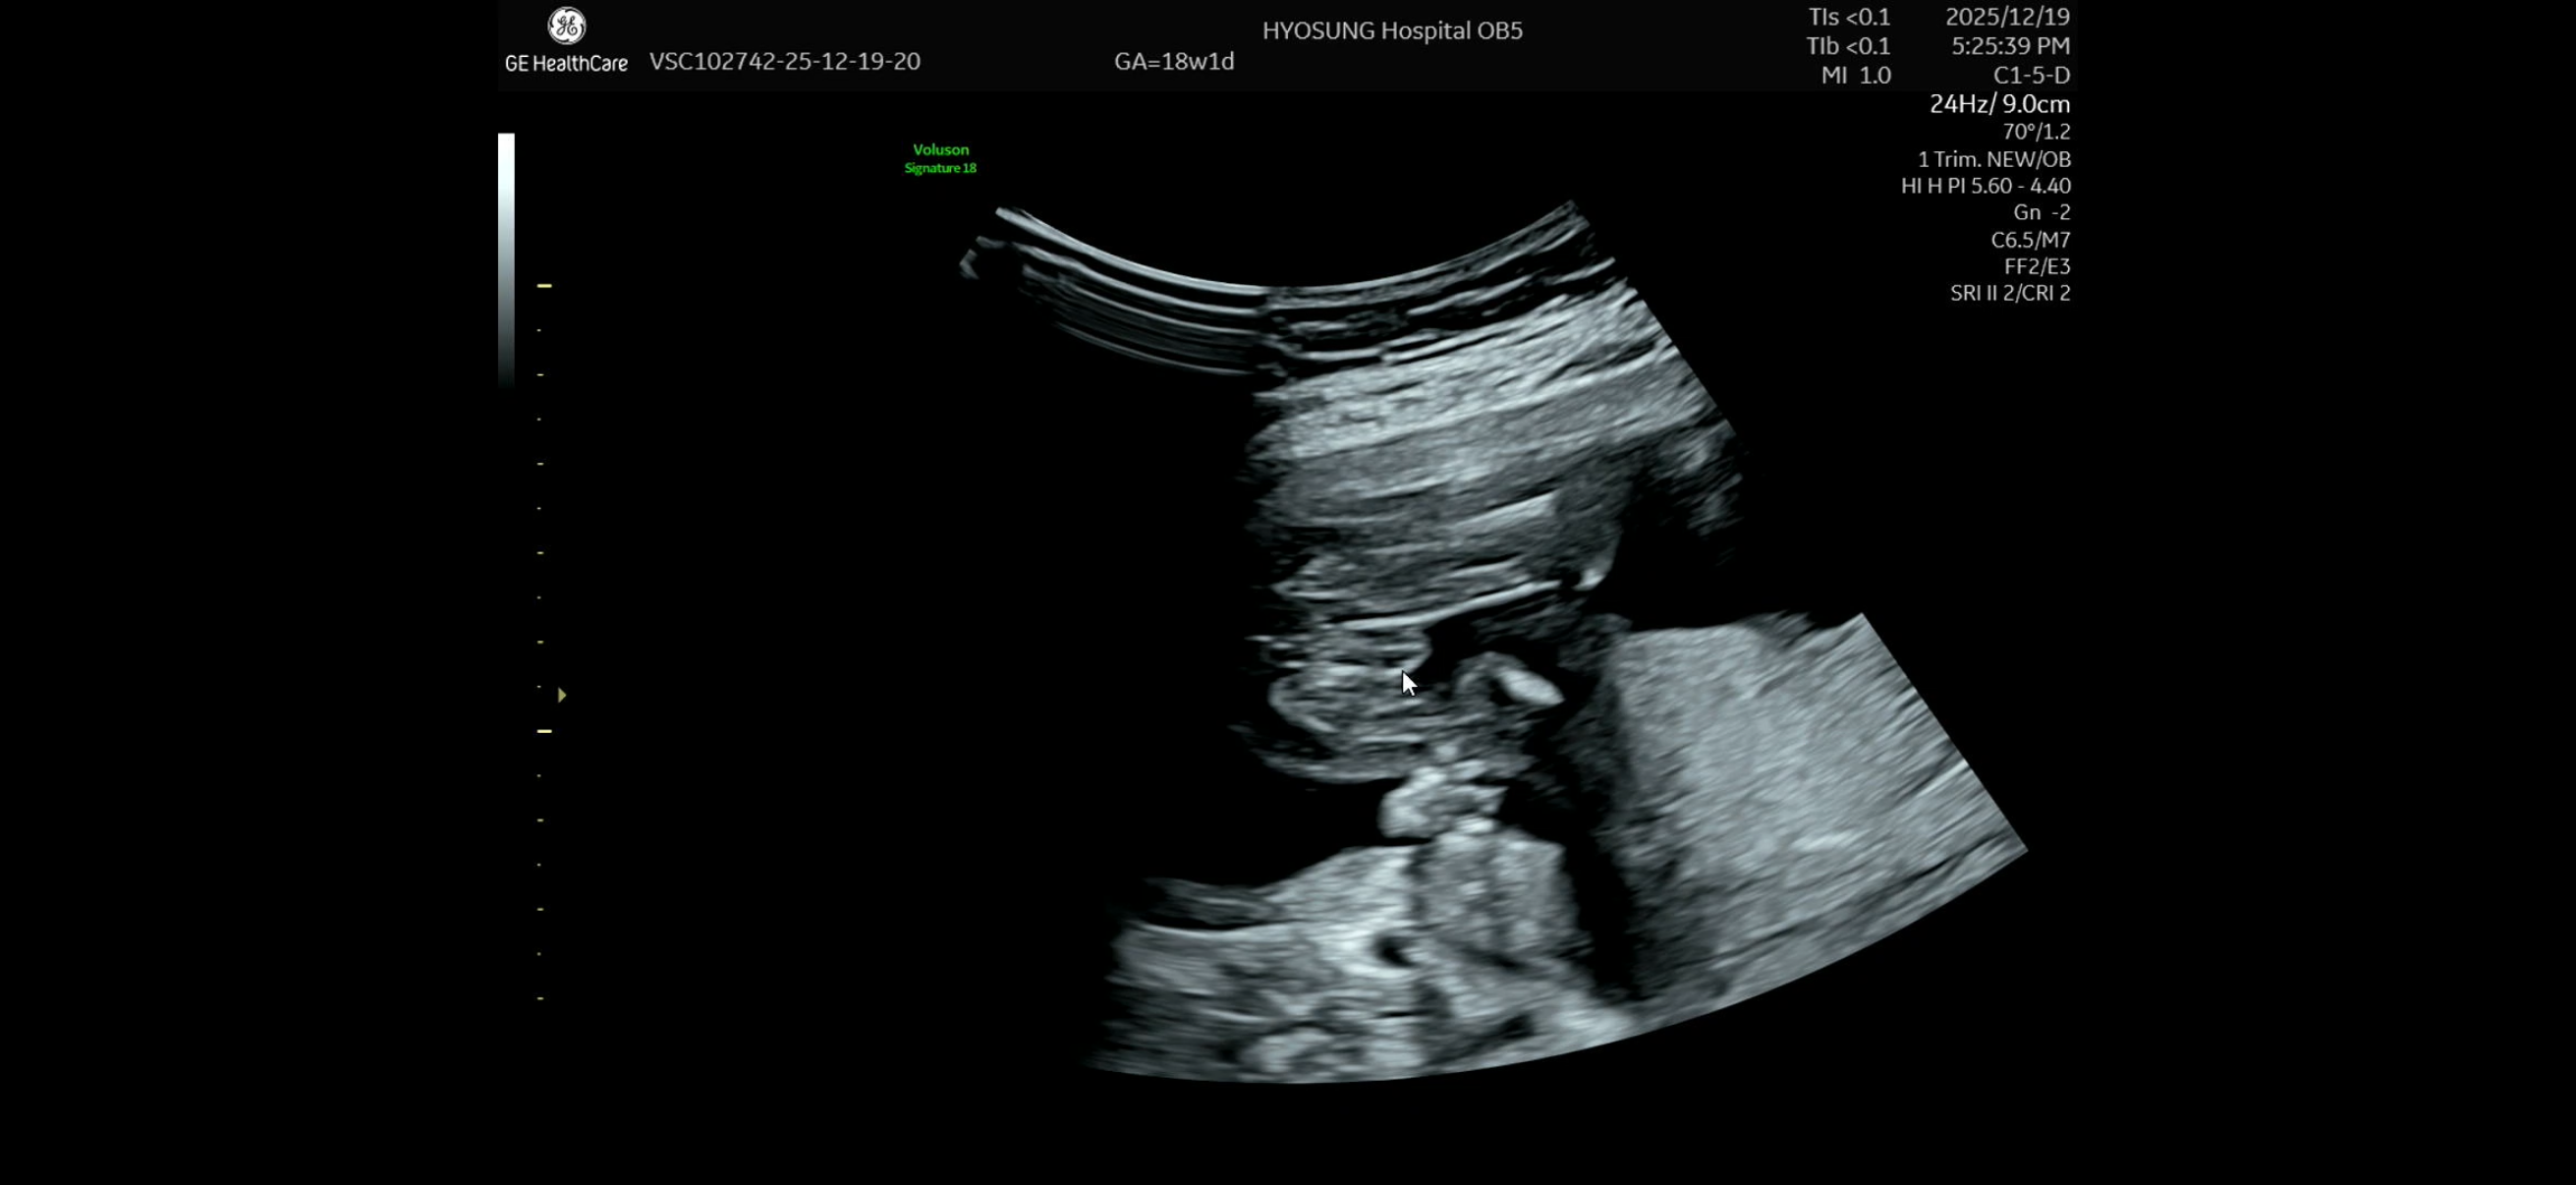

16주차에 양반다리하고 있어서 18주차에 갔는데, 쌤이 아들로 보인다 하시면서도 성별반전될 수 있다고도 하시는데😅 확신의 아들일까요?ㅋㅋ 아니면 딸일까요?

저렇게 세모..? ㅜ ㅜ 로 보이면 아들이래요